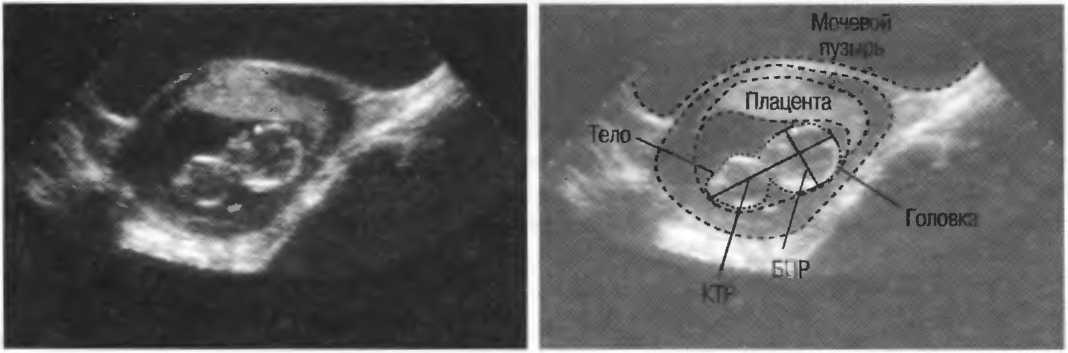

Авторы понимают, что данное руководство не будет отвечать потребностям каждого. Приветствуются все комментарии и предложения, которые будут иметь значительную ценность для последующих изданий. Корреспонденцию следует адресовать руководителю отделения медицинской радиологии. Всемирная организация здравоохранения, 1211 Женева 27, Швейцария.